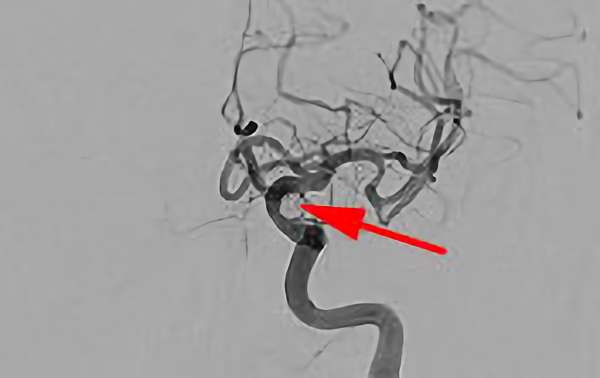

No.1630 手術前